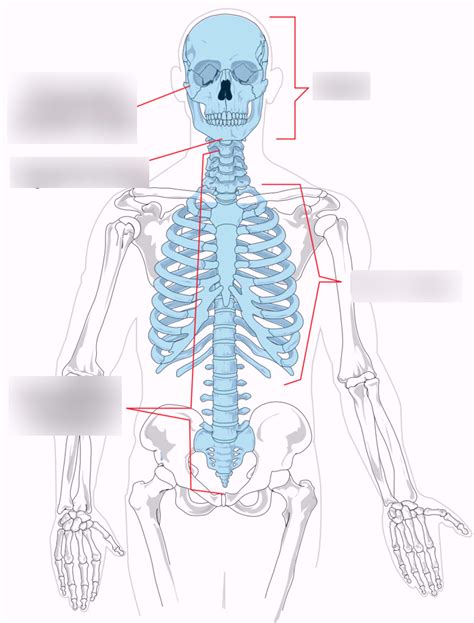

Hey guys, let’s dive deep into the axial skeleton , which is basically the central framework of your body. Think of it as the main support beam for your entire existence. This isn’t just a random collection of bones; it’s a super organized system that protects your vital organs and allows you to move. The axial skeleton is made up of 80 bones and forms the longitudinal axis of the body. It includes the skull, vertebral column, and the rib cage. Pretty crucial stuff, right? Understanding the axial skeleton is key to grasping how our bodies are structured and how we function. So, buckle up, because we’re about to break down this fascinating part of our anatomy!

First up, let’s talk about the skull . This is arguably the most iconic part of the axial skeleton, and for good reason. It’s like nature’s own custom-built helmet, designed to protect your most precious cargo – your brain! The skull is a complex structure made of multiple bones fused together. In adults, there are 22 bones in the skull, divided into two main groups: the cranial bones and the facial bones. The cranial bones form the braincase, enclosing and protecting the brain. These include the frontal bone (forehead), the two parietal bones (sides and roof), the two temporal bones (sides and base), the occipital bone (back and base), the sphenoid bone (middle part of the base), and the ethmoid bone (anterior part of the base). These bones are united by sutures, which are tough, fibrous joints that allow for some slight movement in infants, enabling the skull to grow, but become completely fused in adults to provide maximum protection. Seriously, these sutures are like nature’s superglue!

The facial bones form the framework of the face. They provide structure for your features, anchor your teeth, and create the cavities for your eyes, nose, and mouth. These include the mandible (lower jaw), the maxilla (upper jaw), the two zygomatic bones (cheekbones), the two nasal bones, the two lacrimal bones, the two palatine bones, the two inferior nasal conchae, and the vomer. The mandible is unique because it’s the only movable bone in the skull (apart from the ossicles in the middle ear), allowing us to talk, chew, and make all those amazing facial expressions. The orbits, or eye sockets, are formed by a combination of cranial and facial bones, providing a safe haven for our eyeballs. The nasal cavity is also a marvel of engineering, lined with mucous membranes that warm, humidify, and filter the air we breathe. The skull isn’t just a protective shell; it’s a functional masterpiece that supports essential sensory organs and allows for vital communication and feeding processes. Pretty cool, huh?

Next on our axial skeleton tour is the vertebral column , or spine. This is the central support structure that runs from your skull down to your pelvis. It’s not just one long bone; it’s actually a series of 26 small bones called vertebrae, stacked one on top of the other. These vertebrae are separated by intervertebral discs, which are like shock absorbers, allowing the spine to bend and twist without grinding bone on bone. The vertebral column is divided into five regions: the cervical, thoracic, lumbar, sacrum, and coccyx. The cervical vertebrae are the seven vertebrae in your neck. They’re the smallest and most delicate, but they support the head and allow for its incredible range of motion – nodding, shaking, and tilting. Think about how much movement your neck does every single day; it’s pretty mind-blowing!

The thoracic vertebrae are the twelve vertebrae in your upper and middle back. They are larger than the cervical vertebrae and are characterized by long, pointed spinous processes that project downward. Each thoracic vertebra articulates with a pair of ribs, forming the posterior part of the rib cage. This region is less flexible than the cervical or lumbar regions, providing stability for the upper body. Then we have the lumbar vertebrae , the five vertebrae in your lower back. These are the largest and strongest vertebrae because they bear most of the body’s weight. They have shorter, thicker spinous processes and are built for strength and support. Below the lumbar vertebrae are the sacrum and the coccyx . The sacrum is a triangular bone formed by the fusion of five vertebrae, located at the base of the spine, connecting the vertebral column to the pelvis. The coccyx, or tailbone, is a small, fused bone at the very end of the vertebral column, typically consisting of four fused vertebrae. It’s a remnant of our evolutionary past, but it still serves as an attachment point for some muscles and ligaments. The entire vertebral column is crucial for posture, balance, and protecting the spinal cord, which is the superhighway for nerve signals traveling between the brain and the rest of the body. Without this amazing column of bones, we’d be little more than a blob!

Finally, let’s talk about the rib cage , a marvel of both protection and function. This bony structure encloses and protects your heart and lungs, which are absolutely vital organs. Think of it as a sturdy cage that keeps these delicate structures safe from impact and injury. The rib cage is formed by the ribs , the sternum (breastbone), and the thoracic vertebrae . There are typically 12 pairs of ribs, though some people might have an extra pair. The ribs are long, curved bones that attach posteriorly to the thoracic vertebrae. Anteriorly, most ribs attach directly or indirectly to the sternum.

We can categorize the ribs into three groups: true ribs , false ribs , and floating ribs . The true ribs are the first seven pairs. They attach directly to the sternum via their own costal cartilages. Then there are the false ribs , which are the next three pairs (ribs 8, 9, and 10). Their costal cartilages connect to the cartilage of the rib above them, rather than directly to the sternum. This creates a sort of shared attachment system. Lastly, we have the floating ribs , which are the last two pairs (ribs 11 and 12). These are called floating ribs because they don’t attach to the sternum at all, either directly or indirectly. They just end in the muscles of the abdominal wall. The sternum is a dagger-shaped flat bone located in the center of the chest. It consists of three parts: the manubrium (upper part), the body (middle part), and the xiphoid process (lower, small part). The ribs and sternum work together to form a rigid yet slightly flexible structure that can expand and contract with breathing. When you inhale, your rib cage expands, increasing the volume of your chest cavity, which allows your lungs to fill with air. When you exhale, it contracts. This dynamic movement is essential for respiration. The rib cage also plays a role in protecting other organs in the upper abdomen, like the liver and spleen. It’s truly an indispensable part of the axial skeleton, safeguarding the vital organs that keep us alive and enabling the fundamental process of breathing. Pretty amazing, right?